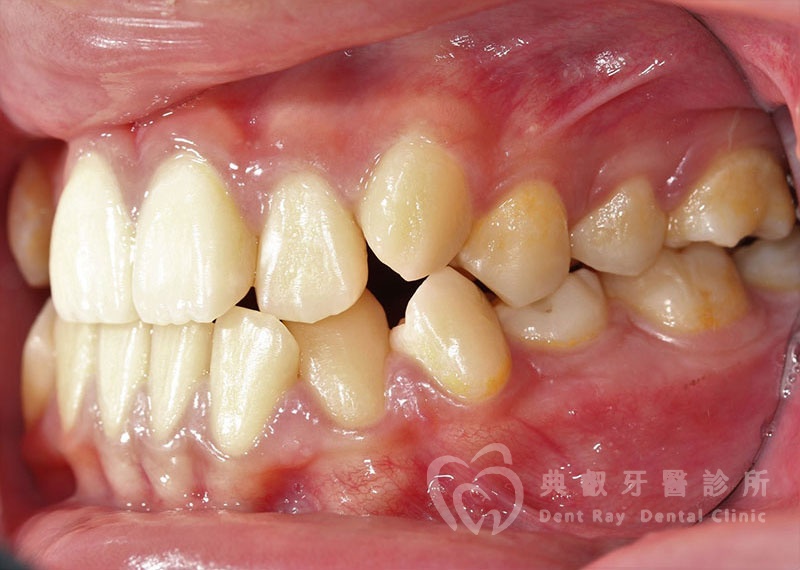

排列擁擠案例一

Before

After